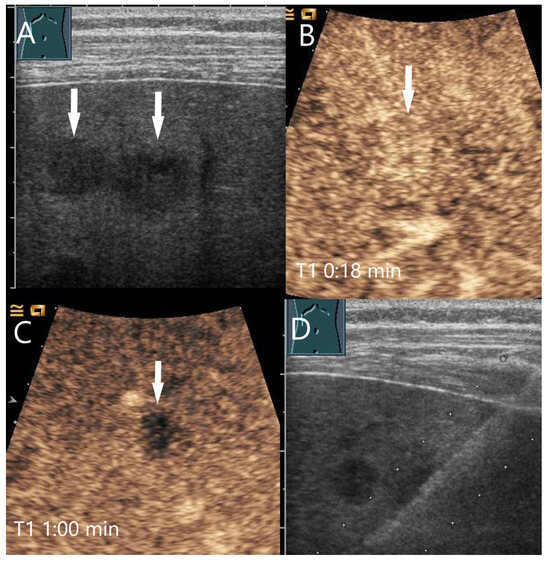

Figure 21.

Sclerosing bile duct adenoma. Female patient with a 31 × 27 mm hypoechoic round liver lesion as an incidental finding (A). The CEUS shows arterial hyperenhancement after 12 s (B) with hyperenhancement with mild predominantly central hypoenhancement after 1 min (C) and 3 min (D). Histological confirmation was performed by US-guided biopsy with histologic diagnosis of a benign sclerosed bile duct adenoma without relevant somatic mutations. This was confirmed by histology after surgical resection.